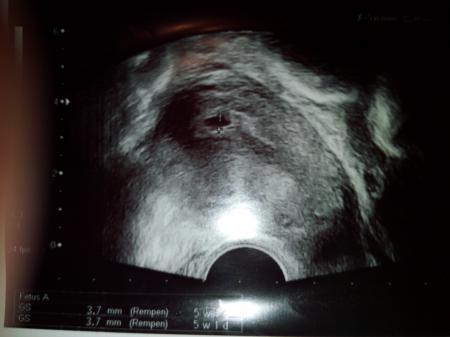

Hallo ihr lieben. Ware heute mal wieder beim Fa. Um Ultraschall und Blutabnahme mache zulassen. Heute bin ich 4+6 und leider könnte Sie nicht 100% die Fruchthöhle bestätigen. Dann frag ich mich was ist das dann auf dem Foto? Und ich darf nächste Woche wieder kommen. Ich dachte mit Kinderwunschk.hat man total viele Termine um die Ohren. Aber das stimmt nicht .darf jetzt mehr zum Fa. Als vorher. War das bei euch auch so.... oder was seht ihr auf dem Foto. Mich nervt das da ist man endlich dann aber dann doch nicht richtig . Vielleicht könnt ihr mir da eure Erfahrungen dazu schreiben. Würde mich freuen und meine angst davon etwas nehmen ...

Bild zu wie war es bei euch??? - Kinderwunschbehandlung